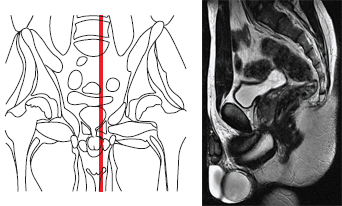

Магнитно-резонансная томография (МРТ) органов малого таза проводятся после предварительного ультразвукового обследования этого анатомического региона.

- высокая разрешающая способность — на магнитно-резонансной томографии (МРТ) органов малого таза можно увидеть объекты размером до нескольких миллиметров и есть возможность получать изображение в любой плоскости;

Желательно проводить исследования органов малого таза на магнитно-резонансном томографе (МРТ) с напряженностью магнитного поля от 1,5 Тесла. В некоторых случаях Вам могут предложить введение внутривенное контрастного вещества для оценки характера процесса и его распространенности.

Магнитно-резонансное исследование (МРТ) органов малого таза 3,0 Т (тесла) не требует специальной подготовки больного, однако как мужчинам, так и женщинам желательно некоторое (не тугое) заполнение мочевого пузыря, то есть перед исследованием не рекомендуется опорожнять мочевой пузырь.